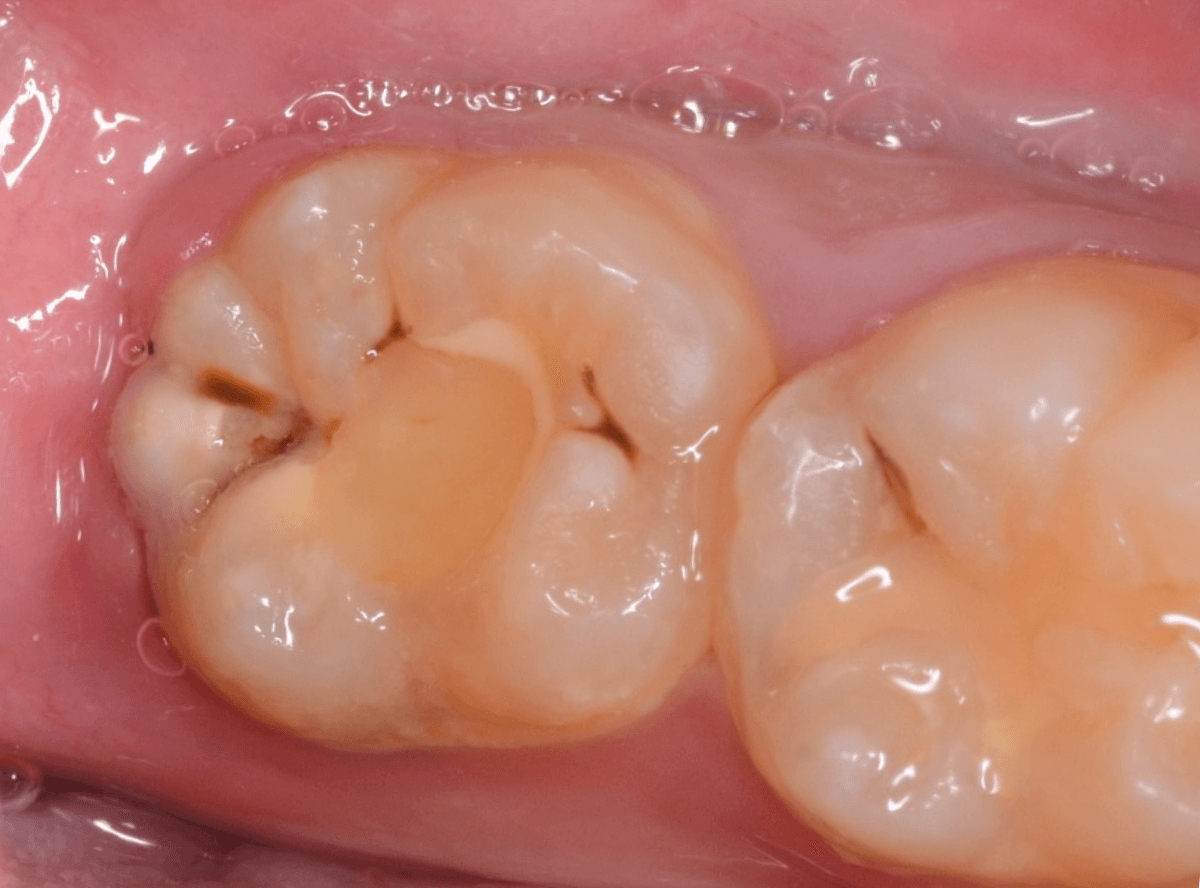

Case.2 レジンの下で神経に触れそうなほどの虫歯

こちらは、下の奥歯の写真です。

特に症状の訴えはありませんでしたが、

歯を観察した瞬間、「虫歯がありそうだな」と思われるような所見です。

私の目には大体このように映っています。

レントゲン写真です。

私が虫歯っぽいと思っていた部分よりも、むしろ手前の部分に大きな虫歯がありました。

もう神経に触りそうな大きな虫歯です。

これだけの虫歯であれば、通常であれば、歯がしみたり、食事中に痛みがあったり何らかの症状があるのですが、無症状のこともあります。

麻酔をして治療開始です。

少し削ると、大きな虫歯が出てきました。

手前の歯にもかかる大きな虫歯でした。

ここまで削っても、まだ、虫歯が残っています。

すぐ下には歯の神経が来ていますから、より慎重に虫歯を除去します。

露髄(歯の神経が見えてしまう事)に怯えながら、慎重に虫歯を除去しました。

なんとか神経ギリギリのところで虫歯がとどまっていました。

虫歯を完全に除去した後、お薬とセメントをつめて経過観察です。

かなり大きな虫歯でしたが、おそらく神経の治療をせずになんとかなりそうです。。。